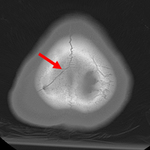

Coronal CT of an open, comminuted, depressed skull fracture. The level of depression is greater than the bony table and there are several bone fragments impacted below the inner cortex of the opposing bone (large arrow). Despite lack of underlying associated brain injury this fracture required operative debridement and elevation of the bone fragments. See also the corresponding sagittal CT image